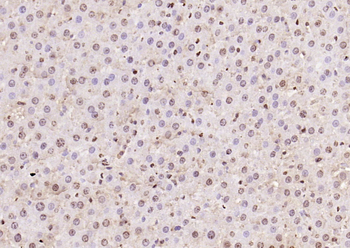

- PPM1D Rabbit Polyclonal Antibody [orb704535]Featured

IF, IHC-Fr, IHC-P

Human, Mouse, Rat

Mouse, Rat

Rabbit

Polyclonal

Unconjugated

100 μl, 50 μl, 200 μl - HSC70 Mouse Monoclonal Antibody [orb704174]Featured